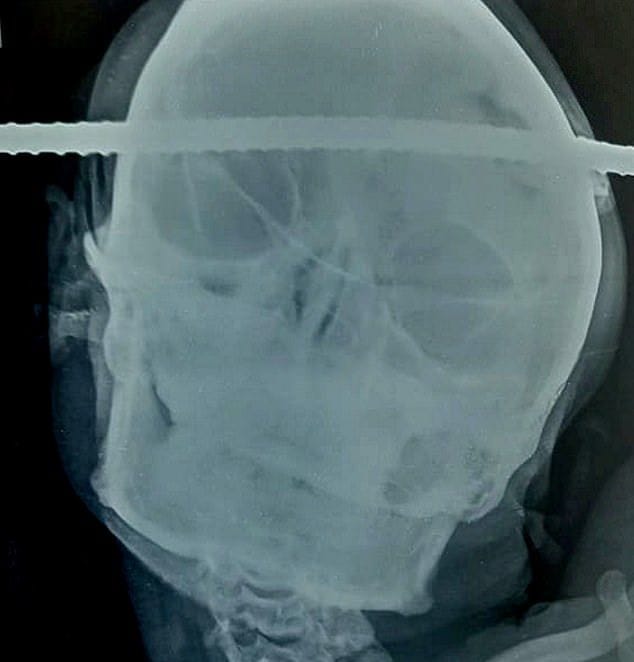

gif_animation インドにて、21歳の建築作業員が足場から落下し、金属の棒が頭蓋骨を貫通するという事故。恐ろしい負傷具合にも関わらず、作業員の男性は命に別状はなく、後遺症も残らないであろうとの事。まさに奇跡・・・。[5]images